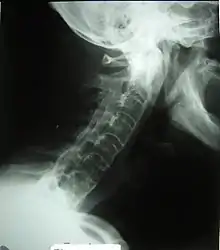

![]() Columna vertebral anquilosada. Se produce una fusión de las vértebras afectadas. | ||